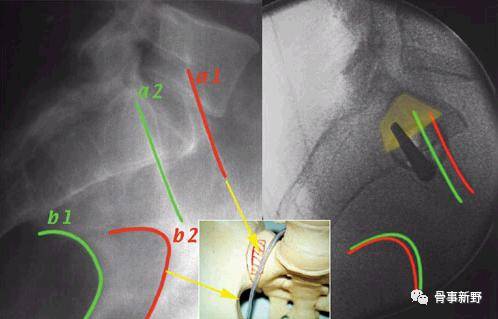

侧位:a1、a2代表双侧坐骨大孔;b1、b2:代表骶骨翼

(4)骶髂螺钉的定位:导针进针点在髂后上、下嵴之间,髂后上嵴外约2横指、坐骨大切迹上方2横指。透视确认入针点,正位、入口位及出口位满意后(在正位图像中导针尖部位于在S1椎体阴影中,出口位导针指向S1椎体中间1/3份,导针位于S1椎体上终板附件的骨质最厚处)。打入导针到中线,一共穿过3层皮质骨,透视位置确认后进行钻孔。